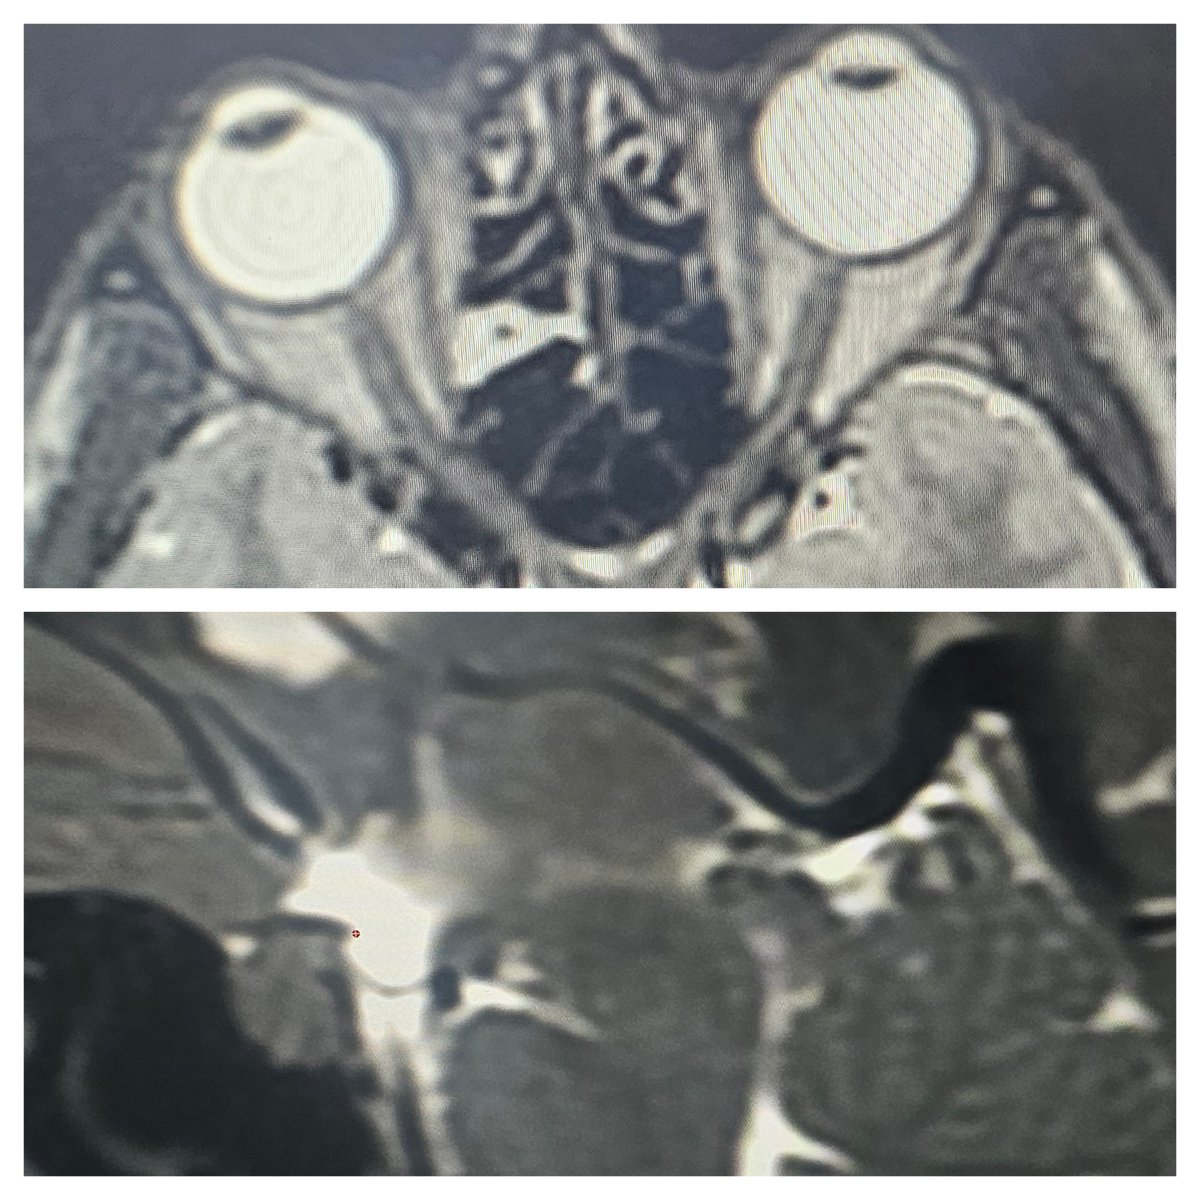

Progression of spontaneous subdural hematomas in a young man over a 3 month period with an untreated lateral #spinalCSFleak. Various barriers to receiving care. He requested surgical repair so he could travel overseas without worrying about the hematomas. ⁦@spinalCSFleak